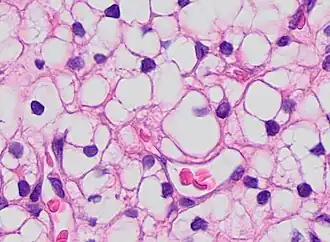

Histopathology

Micrograph showing contraction band necrosis, a histopathologic finding of myocardial infarction (heart attack).